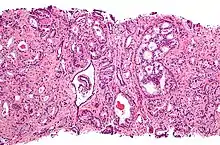

Most prostate cancers are classified as adenocarcinomas, or glandular cancers, that begin when semen-secreting gland cells mutate into cancer cells. The region of the prostate gland where the adenocarcinoma is most common is the peripheral zone. Initially, small clumps of cancer cells remain within otherwise normal prostate glands, a condition known as carcinoma in situ or prostatic intraepithelial neoplasia (PIN). Although no proof establishes that PIN is a cancer precursor, it is closely associated with cancer. Over time, these cells multiply and spread to the surrounding prostate tissue (the stroma) forming a tumor.

Histopathologic diagnosis

A histopathologic diagnosis mainly includes assessment of whether a cancer exists, as well as any subdiagnosis, if possible. Histopathologic subdiagnosis has implications for the possibility and methodology of Gleason scoring.[85] The most common histopathological subdiagnosis is acinar adenocarcinoma, constituting 93% of diagnoses.[86] The most common form of acinar adenocarcinoma, in turn, is "adenocarcinoma, not otherwise specified", also termed conventional, or usual acinar adenocarcinoma.[87]

The Gleason grading system is used to help evaluate the prognosis and helps guide therapy. A Gleason score is based upon the tumor's appearance.[89] Cancers with a higher Gleason score are more aggressive and have a worse prognosis. Pathological scores range from 2 through 10, with a higher number indicating greater risks and higher mortality.

After a biopsy, a pathologist examines the samples under a microscope. If cancer is present, the pathologist reports the grade of the tumor. The grade tells how much the tumor tissue differs from normal prostate tissue and suggests how fast the tumor is likely to grow. The pathologist assigns a Gleason number from 1 to 5 for the most common pattern observed under the microscope, then does the same for the second-most common pattern. The sum of these two numbers is the Gleason score. The Whitmore-Jewett stage is another method.